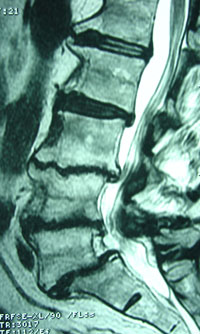

Well, at Manchester Chiropractic & Sports Injuries, we discern that the discs in your spine are 80% water when they are young and healthy. As you get older and with damage, the discs lose water and that advances to the condition called disc degeneration.

To accentuate this characteristic, a study proclaims that lower back pain influences up to 85% of all persons at some time in life. Also, lower back pain is a predicament for which spinal manipulation has been shown to be beneficial. Researchers study steps that can revamp the productiveness of spinal manipulation. One such action, hydration status, was analyzed: The spinal discs of 8 women and 11 men with lower back pain of 1 to 12 months’ length were normal or underhydrated and then hypohydrated for 36 hours before having spinal manipulation. (1) All they did was increase water intake for the 36 hours prior to their spinal manipulation sessions (which we know our Manchester chiropractic patients could easily do!).